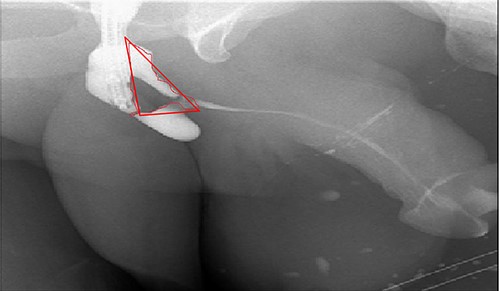

A 38-year-old male was referred to our tertiary hospital due to recurrent urethral stricture for further evaluation and management. His history revealed multiple failed attempts of DVIU, anastomotic urethroplasty and urethroplasty with pedicled fasciocutaneous flap in 2019. Nine months after his surgery, he had complete retention due to stricture recurrence and he underwent multiple dilatations and DVIU but his stricture keep recurring. He was referred to us for definitive management. He was on a suprapubic catheter. Initial workup included retrograde, antegrade cystoscopy and urethrogram. First, an antegrade cystoscope was introduced. The bladder neck, internal sphincter and verumontanum were identified. However, there was no external sphincter due to damage from the previous procedures. A pinpoint opening in the dorsal area of the urethra was seen about 1-cm distal to the verumontanum (Fig. 1, lumen A). Also, a blind-ended urethra in the ventral area was identified (Fig. 2, lumen B). It is most likely from the previous flap. Additionally, the retrograde urethrogram showed that the contrast was only going from the pinpoint hole in the dorsal side of the urethra Fig. 3. Retrograde cystoscopy also showed a blind-ended in the proximal bulbar urethra. We could not identify the small hole that we saw from the antegrade cystoscopy. After initial workup, he was counseled in the clinic for dorsal only buccal mucosal graft (BMG) urethroplasty for which he agreed.

Antegrade (3–1) and retrograde (3–2) urethrogram showing the contrast passing through the pinpoint hole in the dorsal side of the urethra as pointed in black arrow, lumen A; antegrade (3–1) and retrograde (3–2) urethrogram showing a blind ended urethra in the ventral side of the urethra as pointed in red arrow, lumen B.